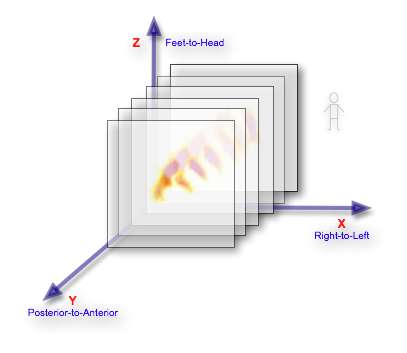

Its helpful, before proceeding, to consider the axial slices, be they SPECT or CT, stacked one behind the other, as illustrated below:

Notice that the figure illustrates each image as a thin slice when the data represents in reality a slice wide enough to fill the gap between it and the next slice, so that the image data can be considered to be a matrix of volume elements - called voxels for short.

A convention applied in medical imaging is to display axial image stacks with the axes oriented as shown in the following figure: